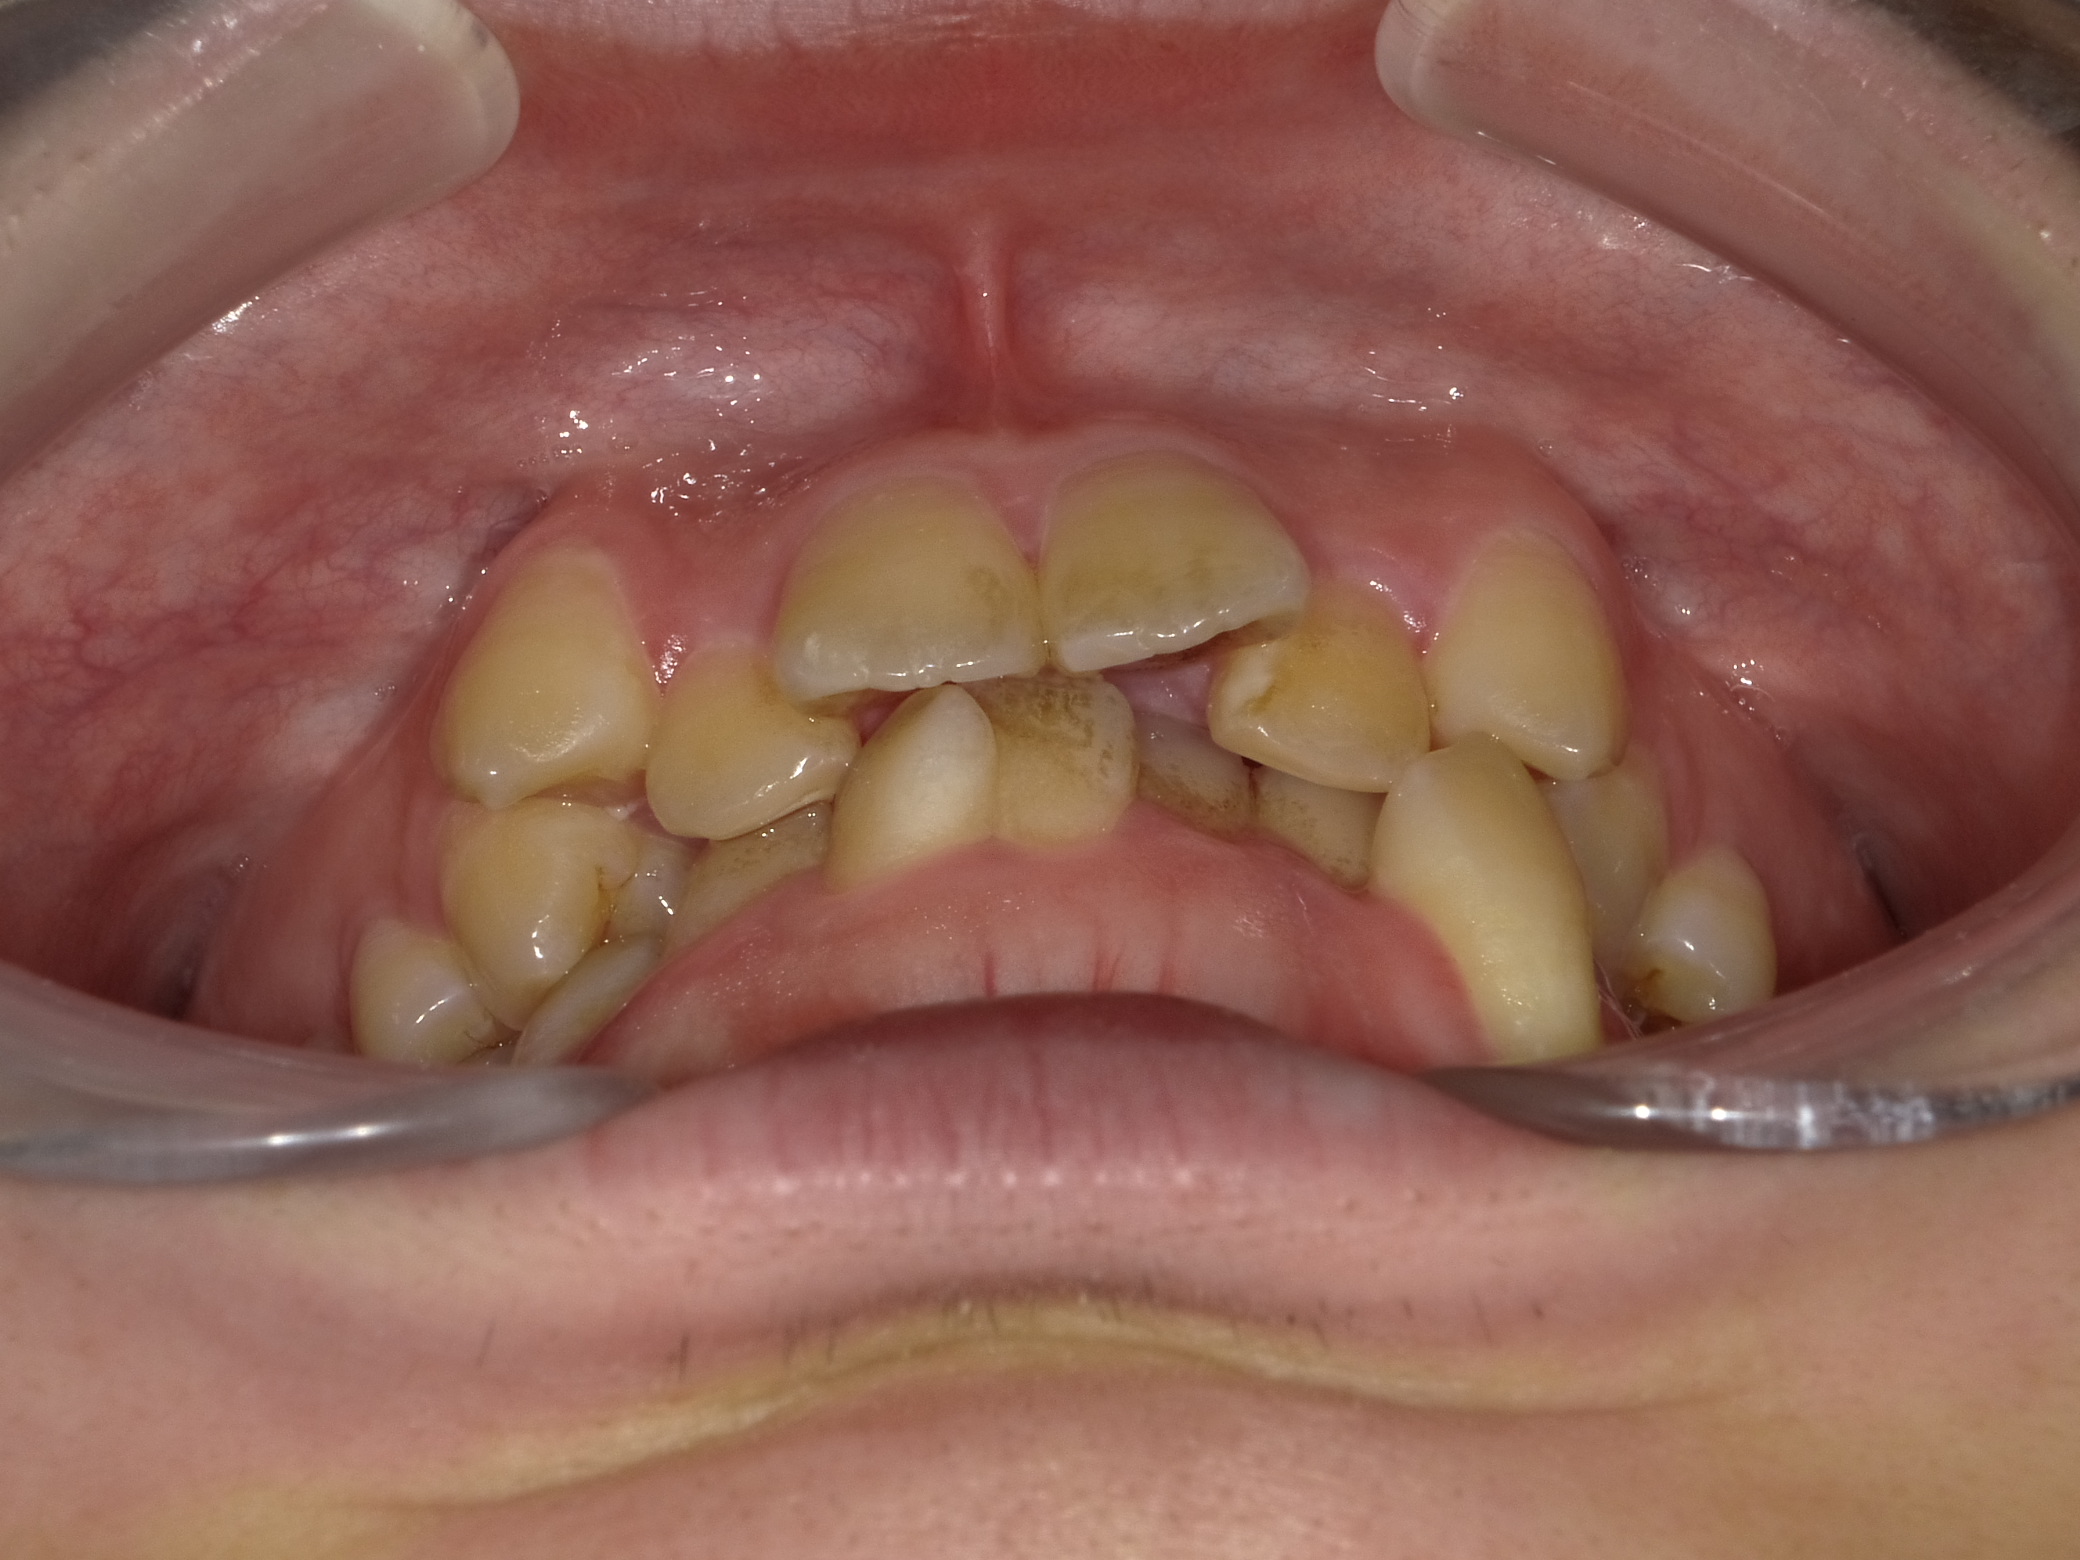

乱ぐい歯 叢生がキツイ症例。 ①

いわゆる「乱杭歯」「重なりが強いガタガタ」の歯並びです。

正面から見るだけでも八重歯や上下の重なりが強く、特に左下の犬歯は位置のズレが大きく根っこが露出してしまっています。

「根っこが露出」=「重度の歯周病」のようなものなので、将来この部位にさらに歯周疾患が起こることで、歯の寿命が著しく短くなる可能性があります。

下から覗くとより歯並びの窮屈感が分かります。

ここまで重なりが強いと、「見た目」うんぬんだけではなく、「噛み合わせ」「歯磨きのしやすさ」etcあらゆる面で矯正治療を行った方がプラスに働くと思います。